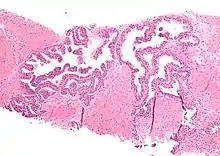

| Micrograph showing high-grade prostatic intraepithelial neoplasia. H&E stain. | |

High-grade prostatic intraepithelial neoplasia (HGPIN) is an abnormality of prostatic glands and believed to precede the development of prostate adenocarcinoma (the most common form of prostate cancer).[1][2]

Histology

HGPIN typically has one of four different histologic patterns:[2]

- tufted (fascicular patterning)

- micropapillary,

- cribriform and,

- flat.

Its cytologic features are that of prostatic adenocarcinoma:

- presence of nucleoli,

- increased nuclear-to-cytoplasmic ratio and,

- increased nuclear size.

Microscopically, PIN is a collection of irregular, atypical epithelial cells. The architecture of the glands and ducts remains normal. The epithelial cells proliferate and crowding results in a pseudo-multilayer appearance. They remain fully contained within a prostate acinus (the berry-shaped termination of a gland, where the secretion is produced) or duct. The latter can be demonstrated with special staining techniques (immunohistochemistry for cytokeratins) to identify the basal cells forming the supporting layer of the acinus. In prostate cancer, the abnormal cells spread beyond the boundaries of the acinus and form clusters without basal cells. In HGPIN, the basal cell layer is disrupted but present. PIN is primarily found in the peripheral zone of the prostate (75-80%), rarely in the transition zone (10-15%) and very rarely in the central zone (5%), a distribution that parallels the zonal distribution for prostate carcinoma.[7]